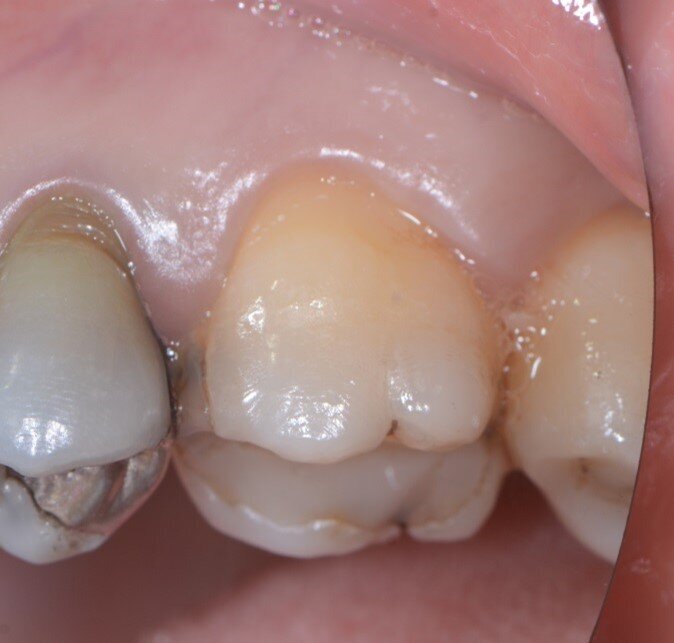

Fig. 8 - Guarigione a 4 mesi